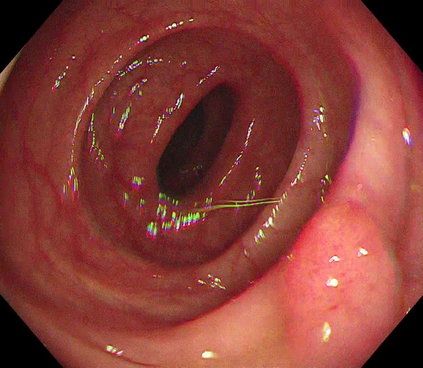

Polyps are early cancer indicators, so assessing occurrences of polyps and their removal is critical. They are observed through a colonoscopy screening procedure that generates a stream of video frames. Segmenting polyps in their natural video screening procedure has several challenges, such as the co-existence of imaging artefacts, motion blur, and floating debris. Most existing polyp segmentation algorithms are developed on curated still image datasets that do not represent real-world colonoscopy. Their performance often degrades on video data. We propose a video polyp segmentation method that performs self-supervised learning as an auxiliary task and a spatial-temporal self-attention mechanism for improved representation learning. Our end-to-end configuration and joint optimisation of losses enable the network to learn more discriminative contextual features in videos. Our experimental results demonstrate an improvement with respect to several state-of-the-art (SOTA) methods. Our ablation study also confirms that the choice of the proposed joint end-to-end training improves network accuracy by over 3% and nearly 10% on both the Dice similarity coefficient and intersection-over-union compared to the recently proposed method PNS+ and Polyp-PVT, respectively. Results on previously unseen video data indicate that the proposed method generalises.